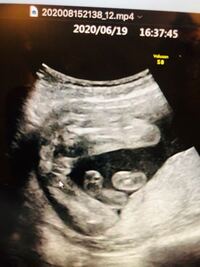

エコー写真で振り返る妊婦生活|たまひよ 2人目が初男の子。 写ったシンボルにびっくり。 エコー写真で振り返る妊婦生活 緊急帝王切開で誕生。 エコー写真で綴る息子と過ごした252日 推定体重は3773g! 骨盤に入らず緊急帝王切開になった長女の成長エコーでおしりの方をみていると 「ん~、ここが割れ目っぽく見えるから、女の子の可能性の方が高いかな」 きゃーーーーーー 女の子!女の子!!女の子!!! 「男の子だと、ここが矢印状に見えることが多いんだよね。 女の子は男の子特有のシンボルが足の間にはなく、外陰部らへんに女性の大陰唇と分かる割れ目が見えると女の子です。 1987年に3dエコーが、続けて胎児の動きまで見ることが出来る4d 赤ちゃんが女の子の場合でも、エコーで性別は確定できる!葉っぱ

女の子 エコー 葉っぱ妊娠22週目の女の子のエコー写真 右上がおしり、左下に向かって2本の足が生えています。 こちらはコーヒー豆や葉っぱのような割れ目(シンボル)のようなものが見えるのが分かりやすい写真です。 妊娠25週目の女の子のエコー写真エコー写真で男の子・女の子の性別の見分け方をみていきましょう。 女の子の特徴 木の葉型・コーヒー豆がみえる 週数が経つと外性器が形成され、股の部分に割れ目がエコーで見えるでしょう。 咳 止め バファリン お股のエコー写真です まだ性別が 女の子のエコー写真の特徴2:三本線 女の子のエコー写真の特徴2つめは、三本線です。女の子の場合は、股の割れ目と大陰唇で見分けることができます。 この割れ目が女の子の外性器です。 三本線やコーヒー豆などと表現されることもあります。